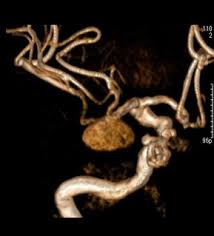

"MRA(Magnetic Resonance Angiography, 자기공명 혈관촬영)"는 MRI를 기반으로 혈관 구조를 영상화한 검사입니다.

- 원리: MRI 기술을 활용하여 혈류 신호를 강조하고, 혈관과 주변 조직을 분리하여 영상화

- 주요 특징: 동맥, 정맥, 혈관 협착, 동맥류 등 혈관 상태 평가에 특화

MRA는 심혈관 질환, 뇌혈관 질환, 말초 혈관 질환 등 혈관 이상 진단에 특히 유용합니다.